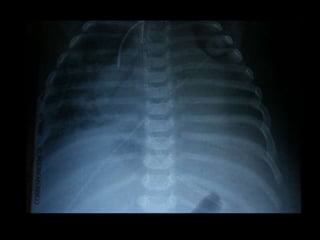

 Radiología: siempre existe cardiomegalia que afecta a

las cuatro cámaras cardiacas. La vascularización

pulmonar esta aumentada y destaca el segmento de

la arteria pulmonar principal

 Radiología: siempreexiste cardiomegalia que afecta a las cuatro cámaras cardiacas. La vascularización pulmonar esta aumentada y destaca el segmento de la arteria pulmonar principal